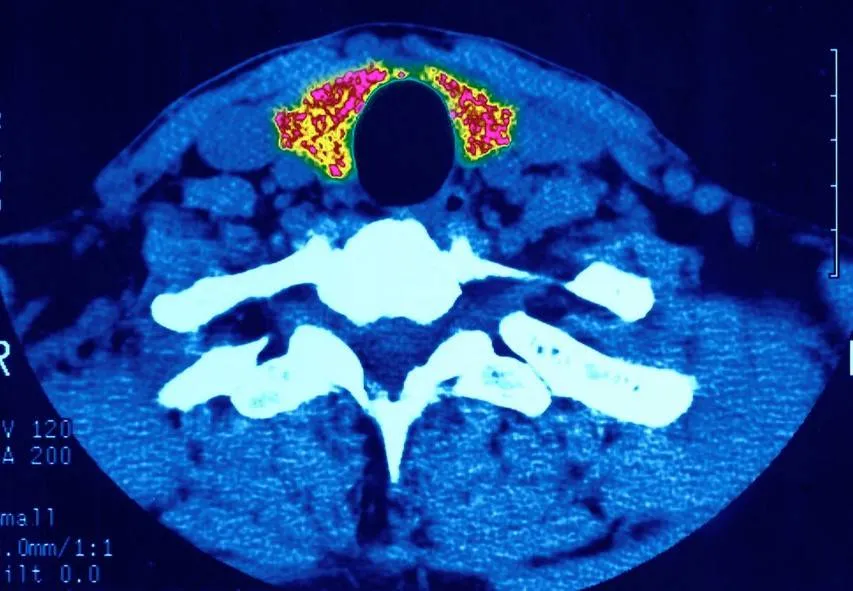

واضافت الطبيبة الروسية أن «قصور الغدة الدرقية وفرط نشاطها وتضخمها ونشوء العقد فيها (التي يمكن أن تؤدي إلى تطور السرطان)، والتهاب الغدة الدرقية المناعي الذاتي أكثر أمراض الغدة الدرقية انتشارا. وتكمن خطورة اضطرابات الغدة الدرقية في أنها غالبا ما تعتبر من أعراض أمراض أخرى».